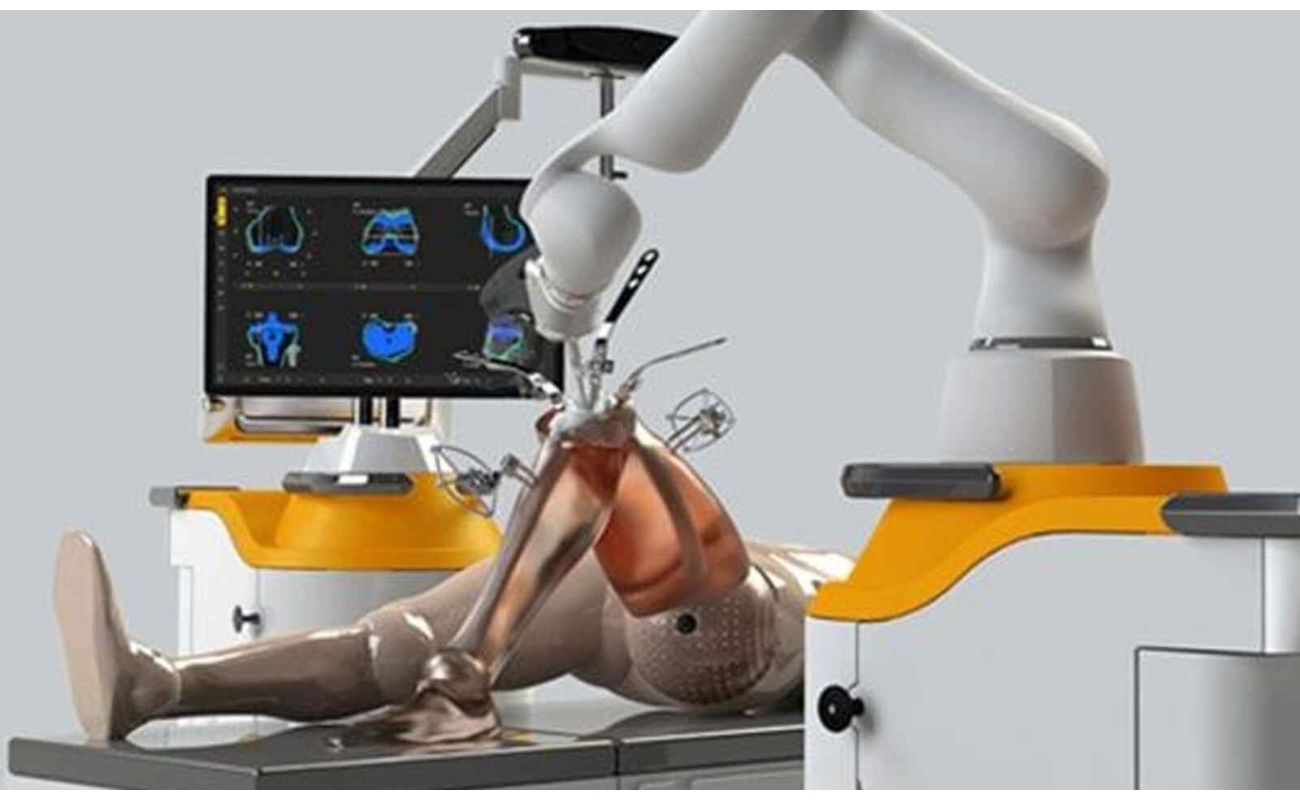

The Benefits of Robotic Knee Replacement Surgery

In recent years, medical technology advancements have brought about a revolution in the field of orthopedic surgery, particularly in the realm of knee replacements.

The Impact of Robotics on Knee Replacement: Revolutionizing Orthopedic Surgery

In recent years, orthopedic surgery has undergone a revolutionary transformation through the integration of robotics in knee replacement procedures.

Knee Replacement Surgery: A Comparison of Traditional and Robotic Techniques

When it comes to addressing debilitating knee pain and restoring mobility, knee replacement surgery has been a transformative solution for many individuals.

Chennai Apollo hospital performs 370 robot-assisted orthopedic procedures in 10 months

A robotic knee replacement is just like a traditional knee replacement. The surgeon removes damaged tissue and replaces it with an artificial joint.